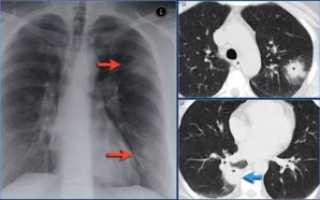

- рентгенографии, на которой можно обнаружить затемнение лёгочных полей различного диаметра, изменение кровеносных сосудов (лёгочного рисунка), уменьшение органа в размерах и смещение тени средостения в сторону поражения;

- компьютерной или магнитно-резонансной томографии, позволяющей выявить изменения лёгочной ткани на самых ранних стадиях.

Для подтверждения диагноза «пневмосклероз» в большинстве случаев хватает проведения одной лишь рентгенографии лёгких.